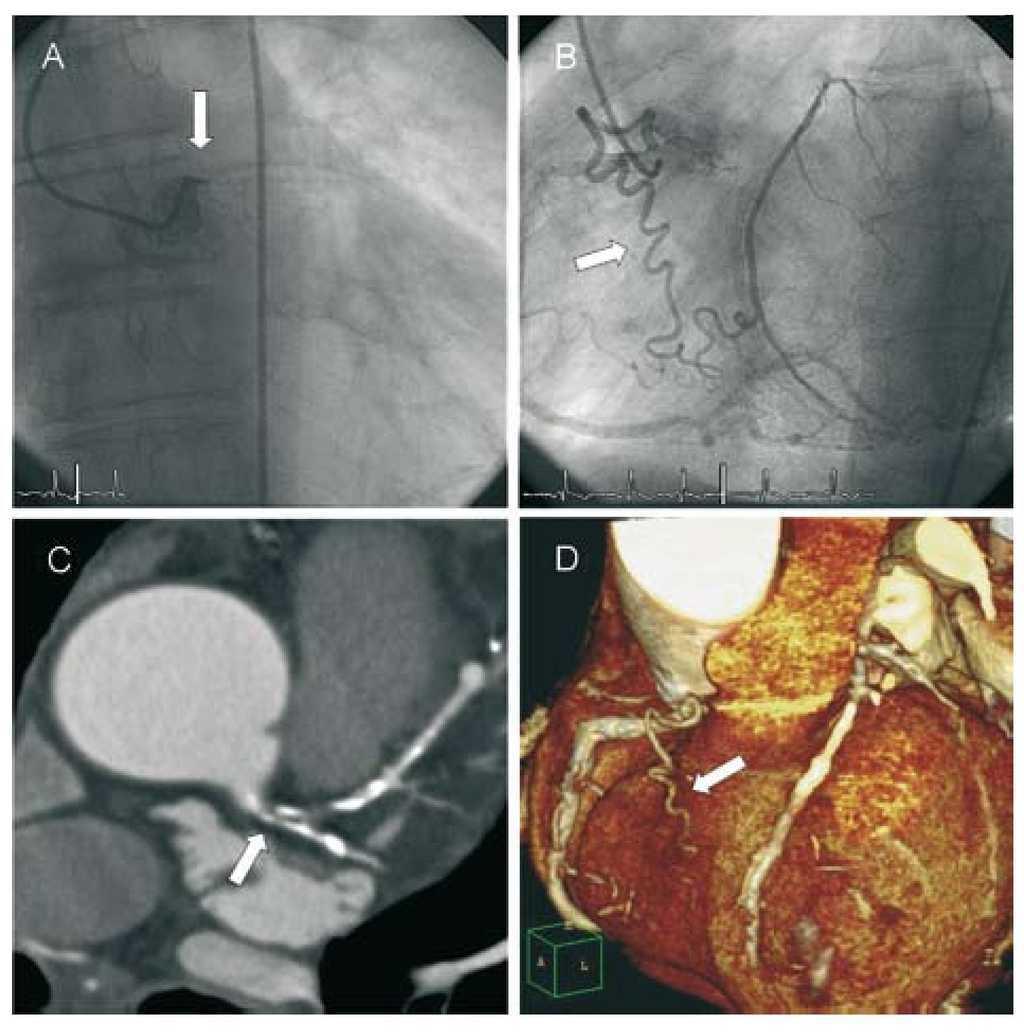

Auto Collateral From The Second Diagonal Branch To The Left Anterior Descending Artery Bmj Case Reports

casereports.bmj.com

Cardiovascular Medicine Unusual Collateralisation Of A Chronic Total Occlusion Of The Left Anterior Descending Artery

cardiovascmed.ch